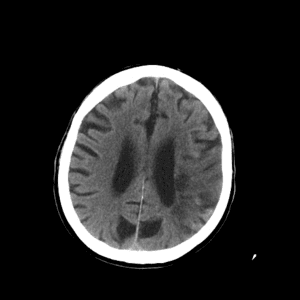

PCA infarct

Case #2